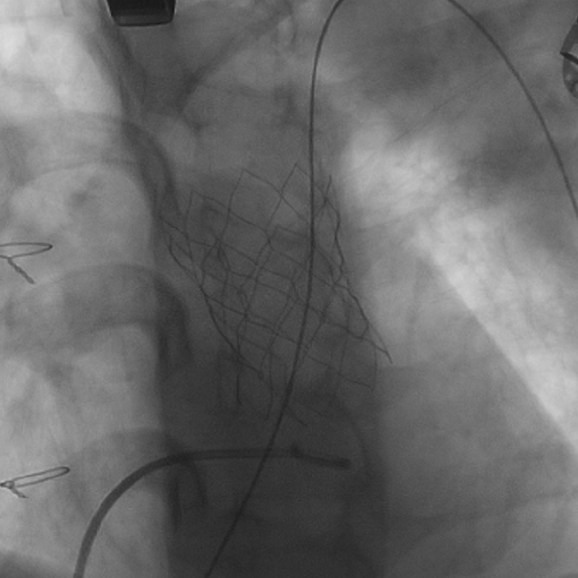

患者女性,21岁,19年前行法洛四联症矫治术,发现肺动脉重度关闭不全2年。术前影像学重建显示提示患者肺动脉最窄截面呈椭圆形,腰部径宽18-24mm。手术经胸小切口入路,术中通过经食道超声,球囊测量、科学评估肺动脉干后,考虑植入30# Salus介入肺动脉瓣。在TEE引导以及DSA造影下,经右室流出道穿刺植入瓣膜,术后TEE提示肺动脉介入瓣植入位置理想、固定良好,无瓣周漏及中央返流。

瓣膜植入后